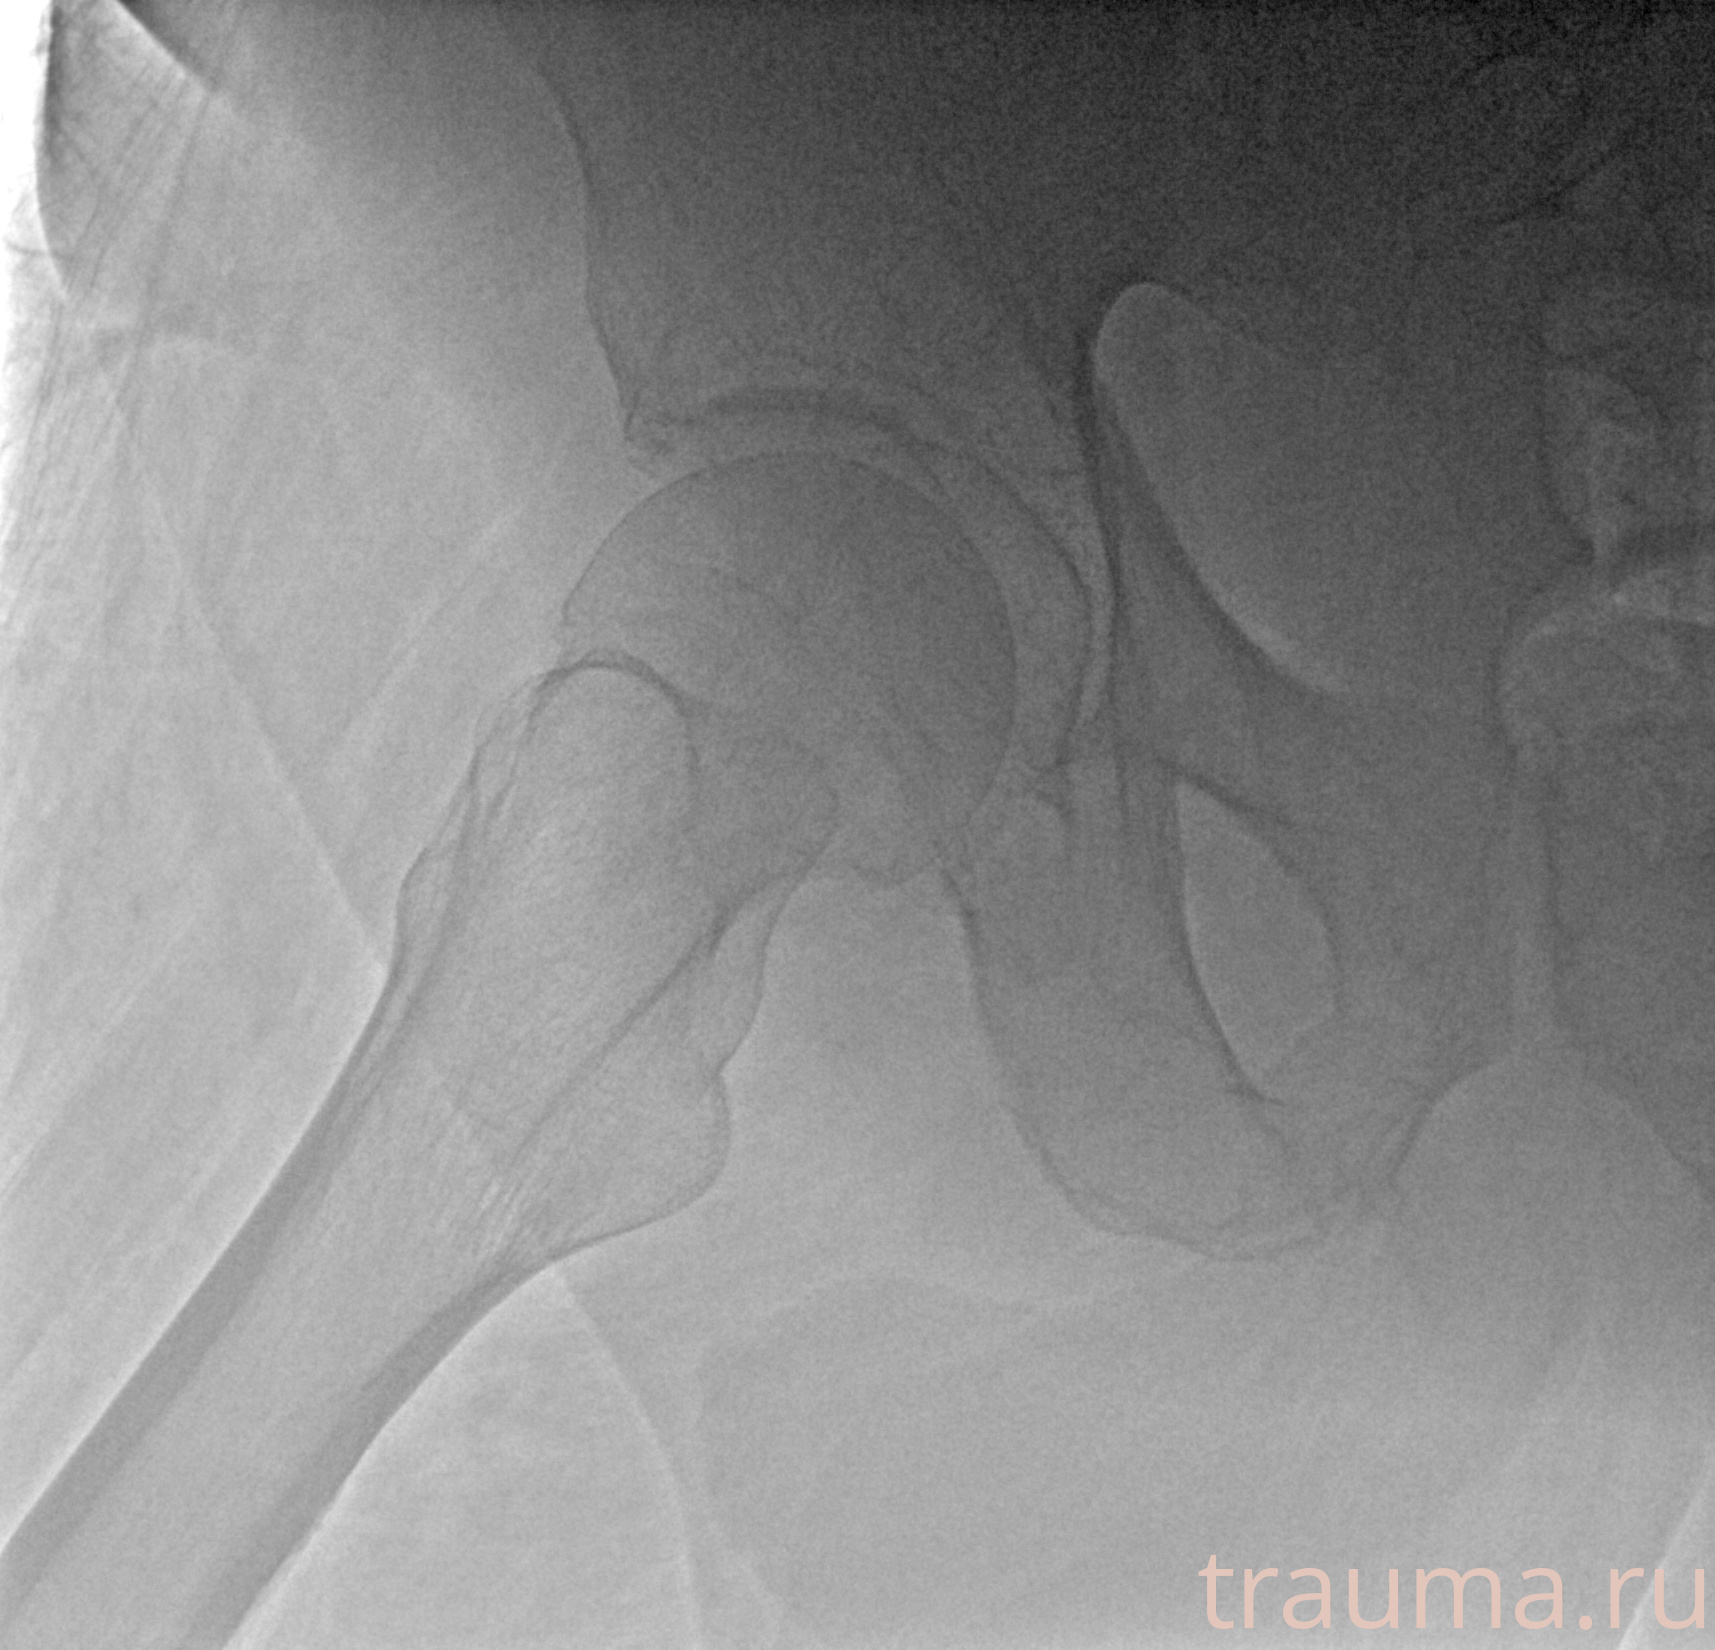

Первая помощь при переломе шейки бедра

Рентгенограммы

Рентген на дому: по вашему адресу приезжает врач-рентгенолог, травматолог-ортопед с мобильным рентгеновским аппаратом, проводит диагностику травмы или заболевания, делает необходимые рентгенограммы, дает рекомендации по дальнейшему лечению. Получить качественные снимки в домашних условиях возможно благодаря уникальной методике, разработанной МосРентген Центром для института  Склифосовского